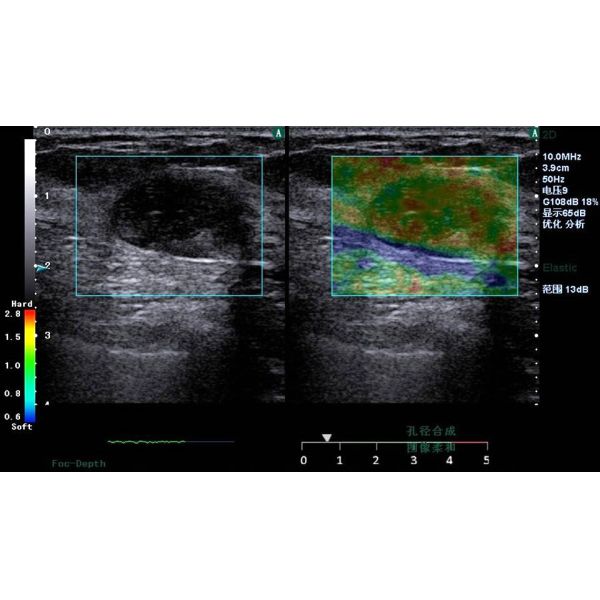

Figure 3. Clinical strain images of confirmed (a) inflammation lesion; (b) benign and (c) malignant breast tumor

2. Freehand elastography

Motion tracking of manual compression or breathing

induced movement generates a strain image

representing the elasticity of the underlying tissue. Statemed